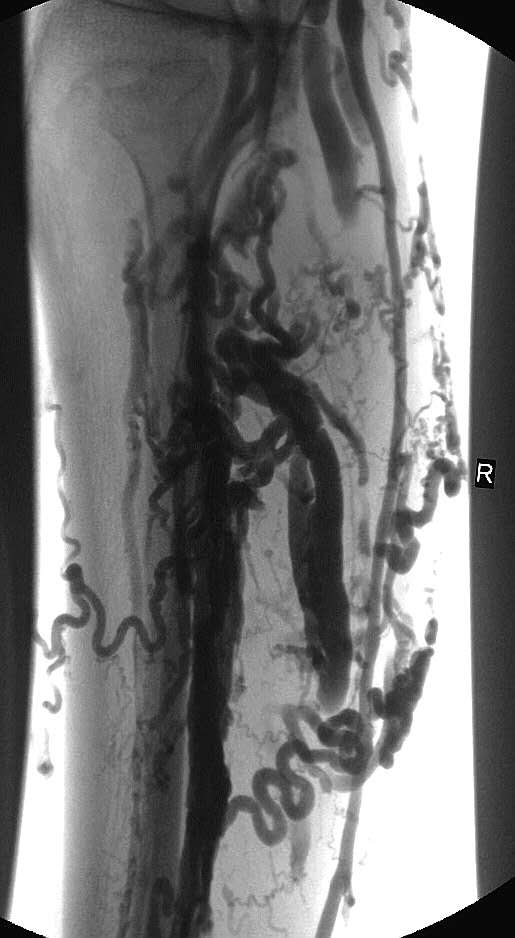

静脉造影显示明显曲张的静脉

近年来,介入微创理念深入人心,介入科往往采用最微创、也特别简便安全的“泡沫硬化术”来处理曲张静脉:直接往曲张静脉腔内注入泡沫硬化剂!因为有DSA影像引导,有静脉造影图像参考,采取分段注射的方式,无须麻醉,安全性高,效果满意,治疗后可以立即下床行走,行动生活不受影响,因而深受欢迎。